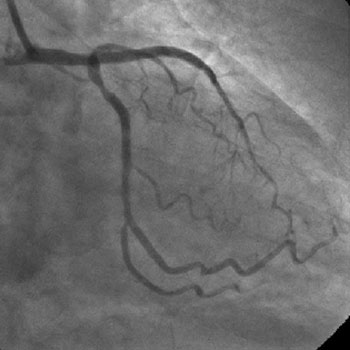

3) LAD: Ostial CTO ( Figure 2) with collaterals from RCA and LCX (Figure 3).